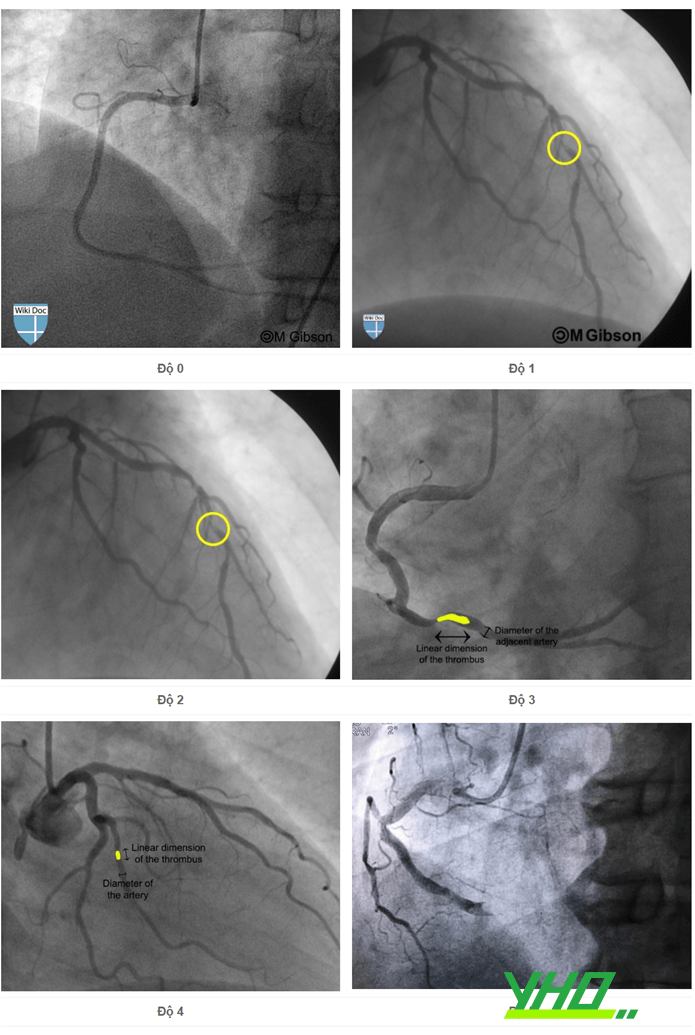

- Đánh giá mức độ huyết khối. Gánh nặng huyết khối được chia thành 6 mức độ:

- Độ 0: Không có huyết khối.

- Độ 1: Khả năng có huyết khối.

- Độ 2: Huyết khối với đường kính lớn nhất < 1/2 đường kính lòng mạch.

- Độ 3: Huyết khối với đường kính lớn nhất > 1/2 và < 2 lần đường kính lòng mạch.

- Độ 4: Huyết khối với đường kính lớn nhất > 2 lần đường kính lòng mạch.

- Độ 5: Huyết khối gây tắc hoàn toàn mạch máu.

Bệnh nhân được phân loại thành: Nhóm có gánh nặng huyết khối thấp (độ 1,2,3) và gánh nặng huyết khối cao (độ 4,5).